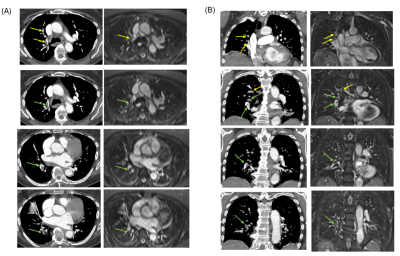

New research on CT technology also figured prominently at the just-concluded American College of Cardiology (ACC) meeting in Chicago. Making waves was a study by researchers from Pennsylvania that added further support to the use of coronary CT angiography (CCTA) to triage patients presenting to the emergency room with chest pain that could be caused by heart disease.

Researchers in the American College of Imaging Network (ACRIN) PA 4005 study followed outcomes of patients who were discharged from the ER following a negative CCTA scan. They found no major adverse events in the 30-day period after patients were discharged, and an overall event rate of less than 1% after a month. Read more by clicking here.